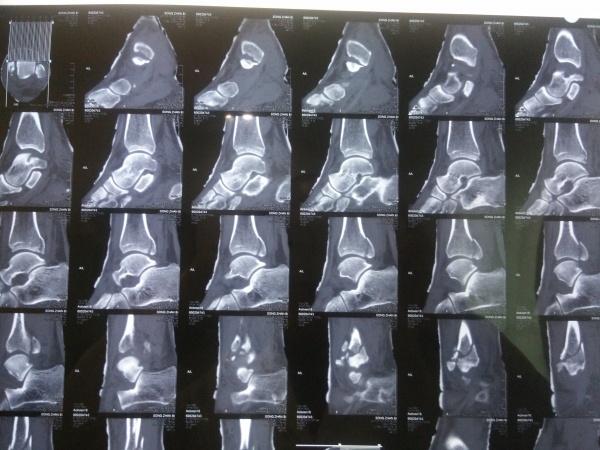

左三踝骨折手术治疗

患者女,外伤后左踝关节活动受限1小时入院,

入院后查体:左踝关节肿胀,活动受限,行DR及左踝关节CT检查,如下图,手术待肿胀消退后行手术治疗,目前愈合良好,请问问各位老师,好久可以下地呀, 下胫腓联合镙钉3个月取呀,